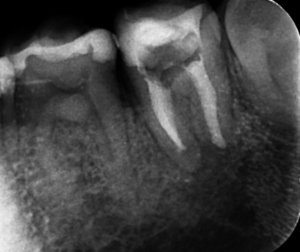

精密再根管治療により膿の改善をはかりました。

根管充填の画像です。近心根の根管は、根尖付近で石灰化していました。

膿の原因になっている遠心根は、根の先までしっかり根管充填ができました。